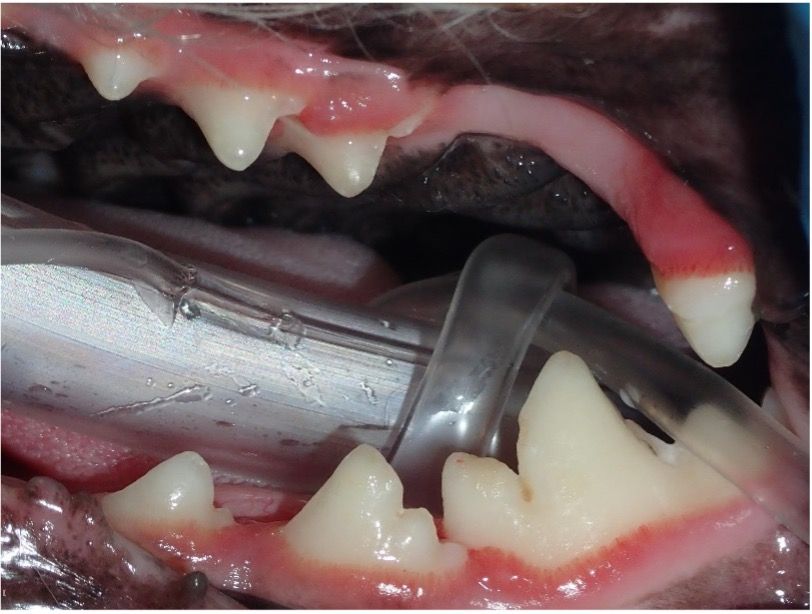

Periodontal disease is the most common disease affecting companion animals today and studies show that by 2 years of age 70% of cats and 80% of dogs have some form of periodontal disease.1,2This staggering statistic implies that a significant portion of puppies and kittens seen for wellness exams will suffer from periodontal disease within 16 months of completing their vaccine appointments. (Figures 1 and 2)

Routine spay or neuter exams offer a prime opportunity for oral health assessments, allowing early intervention for dental abnormalities. The team will assess crowding of teeth (Figure 5) that may allow PD to occur at a faster rate and visualize missing, fractured, displaced teeth causing trauma, and persistent deciduous teeth. This is a perfect time to advocate for baseline dental radiographs (Figure 6) and oral thiol tests to see what is happening under the gum line and decide when their first PRO may be needed.